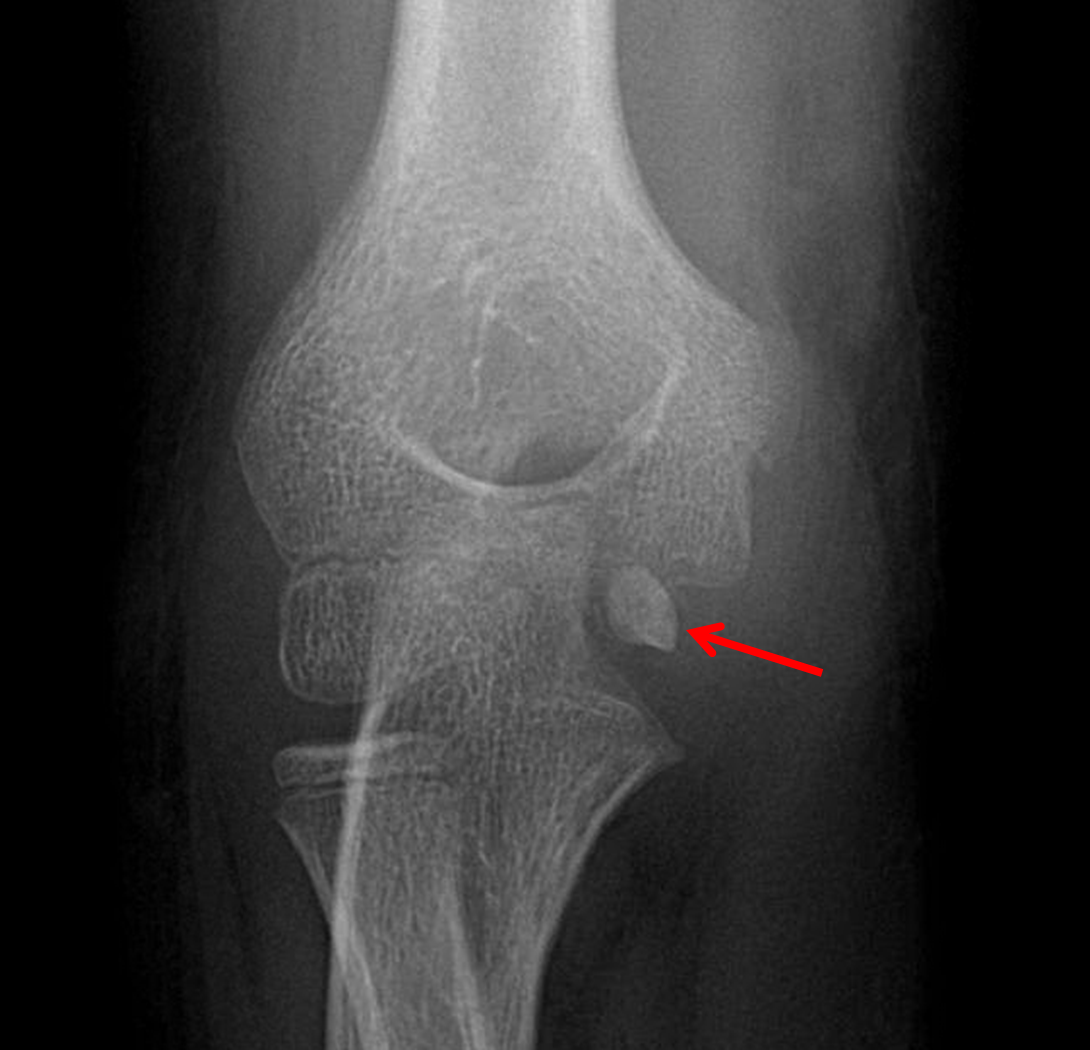

Medial epicondyle avulsion fracture Image Avulsion Fracture Epicondyle trauma resulting in valgus stress on the elbow, such as falling on an outstretched hand or through throwing or wrestling, causes an. medial epicondyle avulsion fractures are of two distinct types. an avulsion fracture is where the muscle or ligament pulls the attachment site of the bone away from its origin. medial epicondylar fractures are the. Avulsion Fracture Epicondyle.

Medial epicondyle avulsion fracture in a 6yearold child after a fall.... Download Scientific Avulsion Fracture Epicondyle trauma resulting in valgus stress on the elbow, such as falling on an outstretched hand or through throwing or wrestling, causes an. an avulsion fracture is where the muscle or ligament pulls the attachment site of the bone away from its origin. medial epicondyle avulsion fractures are of two distinct types. medial epicondylar fractures are the. Avulsion Fracture Epicondyle.

Medial epicondyle avulsion fracture Image Avulsion Fracture Epicondyle a medial epicondyle fracture is an avulsion injury of the attachment of the common flexors of the forearm. trauma resulting in valgus stress on the elbow, such as falling on an outstretched hand or through throwing or wrestling, causes an. an avulsion fracture is where a small piece of bone attached to a tendon or ligament gets. Avulsion Fracture Epicondyle.